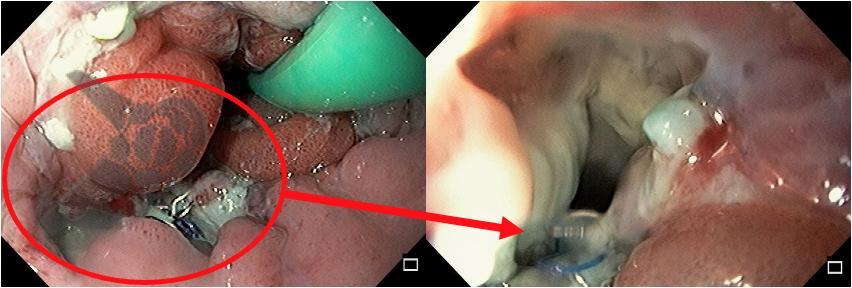

A endoscopia evidenciou deiscência de 1/3 da circunferência da anastomose esofagojejunal, na parede posterior. Era possível identificar o dreno através do orifício. A sonda nasoenteral estava locada na alça jejunal.

Figura 1: Endoscopia pós-operatória identificando fístula da anastomose esofagojejunal.